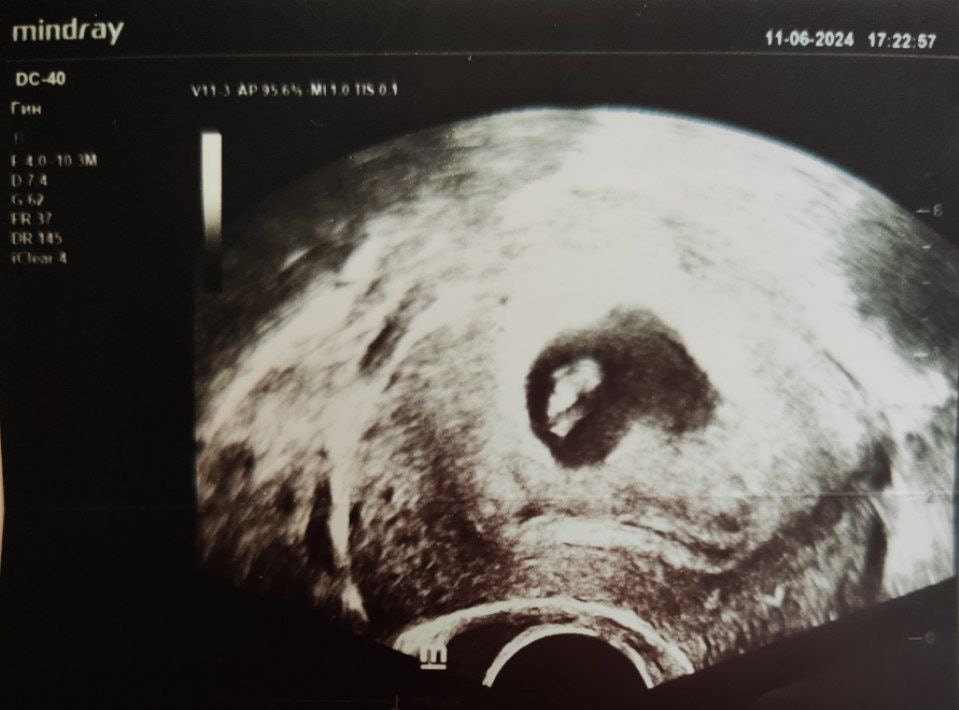

6 недель 6 дней, УЗИ для поиска эмбриона и его СБ (11.06.2024)

Средний диаметр ПЯ 32мм, КТР (копчико-теменное расстояние) 9.2мм, ЖМ 4мм, СБ+